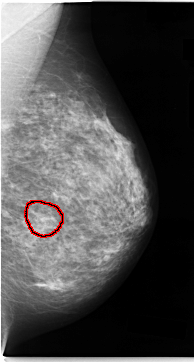

C_0060_1.LEFT_CC

FILE: C_0060_1.LEFT_CC.OVERLAY

TOTAL_ABNORMALITIES 1

ABNORMALITY 1

LESION_TYPE CALCIFICATION TYPE AMORPHOUS DISTRIBUTION CLUSTERED

ASSESSMENT 4

SUBTLETY 2

PATHOLOGY MALIGNANT

TOTAL_OUTLINES 1

BOUNDARY